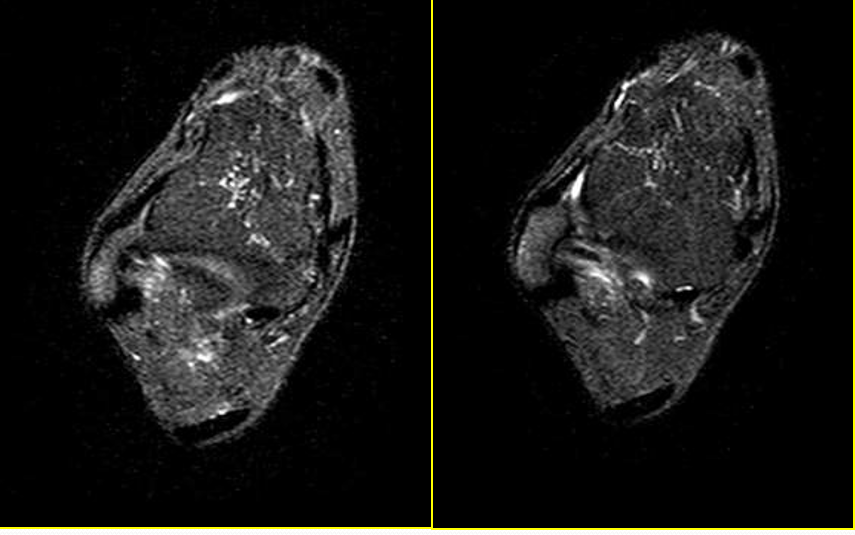

距腓前韧带撕裂

病因病理机制:

• 最脆弱的外侧韧带,也最先断裂

• 内翻内旋伴跖屈

• 距腓前韧带撕裂致内旋受限

• 临床表现为前外踝疼痛,活动受限